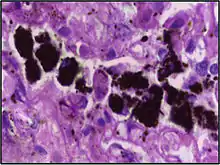

Alveolar macrophages are frequently seen to contain granules of exogenous material such as particulate carbon that they have picked up from respiratory surfaces. Such black granules may be especially common in smoker's lungs or long-term city dwellers.

| Anthracosis | Black-brown granules | Interstitium (perivascular) | ![]() |

Black arrow shows interstitial anthracotic pigment. Nearby macrophages (white arrow) can be presumed to contain anthracotic pigment. | ||